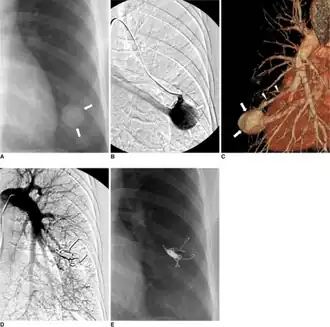

Pulmonary arteriovenous malformation-a) X-ray b) left selective pulmonary arteriogram c) CT angiogram demonstrates pulmonary arteriovenous malformation arrows d) after embolotherapy (placing four Nester coils) e) 19 months after embolotherapy complete disappearance pulmonary arteriovenous malformation shadow

Treatment for brain AVMs can be symptomatic, and patients should be followed by a neurologist for any seizures, headaches, or focal neurologic deficits. AVM-specific treatment may also involve endovascular embolization, neurosurgery or radiosurgery.[6] Embolization, that is, cutting off the blood supply to the AVM with coils, particles, acrylates, or polymers introduced by a radiographically guided catheter, may be used in addition to neurosurgery or radiosurgery, but is rarely successful in isolation except in smaller AVMs.[22] Gamma knife may also be used.[23]

Treatment of lung AVMs is typically performed with endovascular embolization alone, which is considered the standard of care. [24]